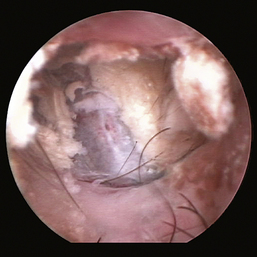

image

Figure 20-10 Bulging pars flaccida in a Cavalier King Charles spaniel dog with primary secretory otitis media. 1, Pars flaccida.

(Courtesy of Dr. Lynette Cole, The Ohio State University, Columbus, Ohio.)